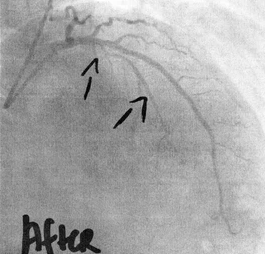

협심증은 관상동맥이 좁아져 발생하는 흉부 통증이라면, 심근경색은 관상동맥이 완전히 막혀 심장근육이 괴사 하면서 발생하는 가슴통증입니다. 따라서 협심증 환자 중 일부는 흉통 없이 호흡곤란만을 호소하기도 한다고 하네요.